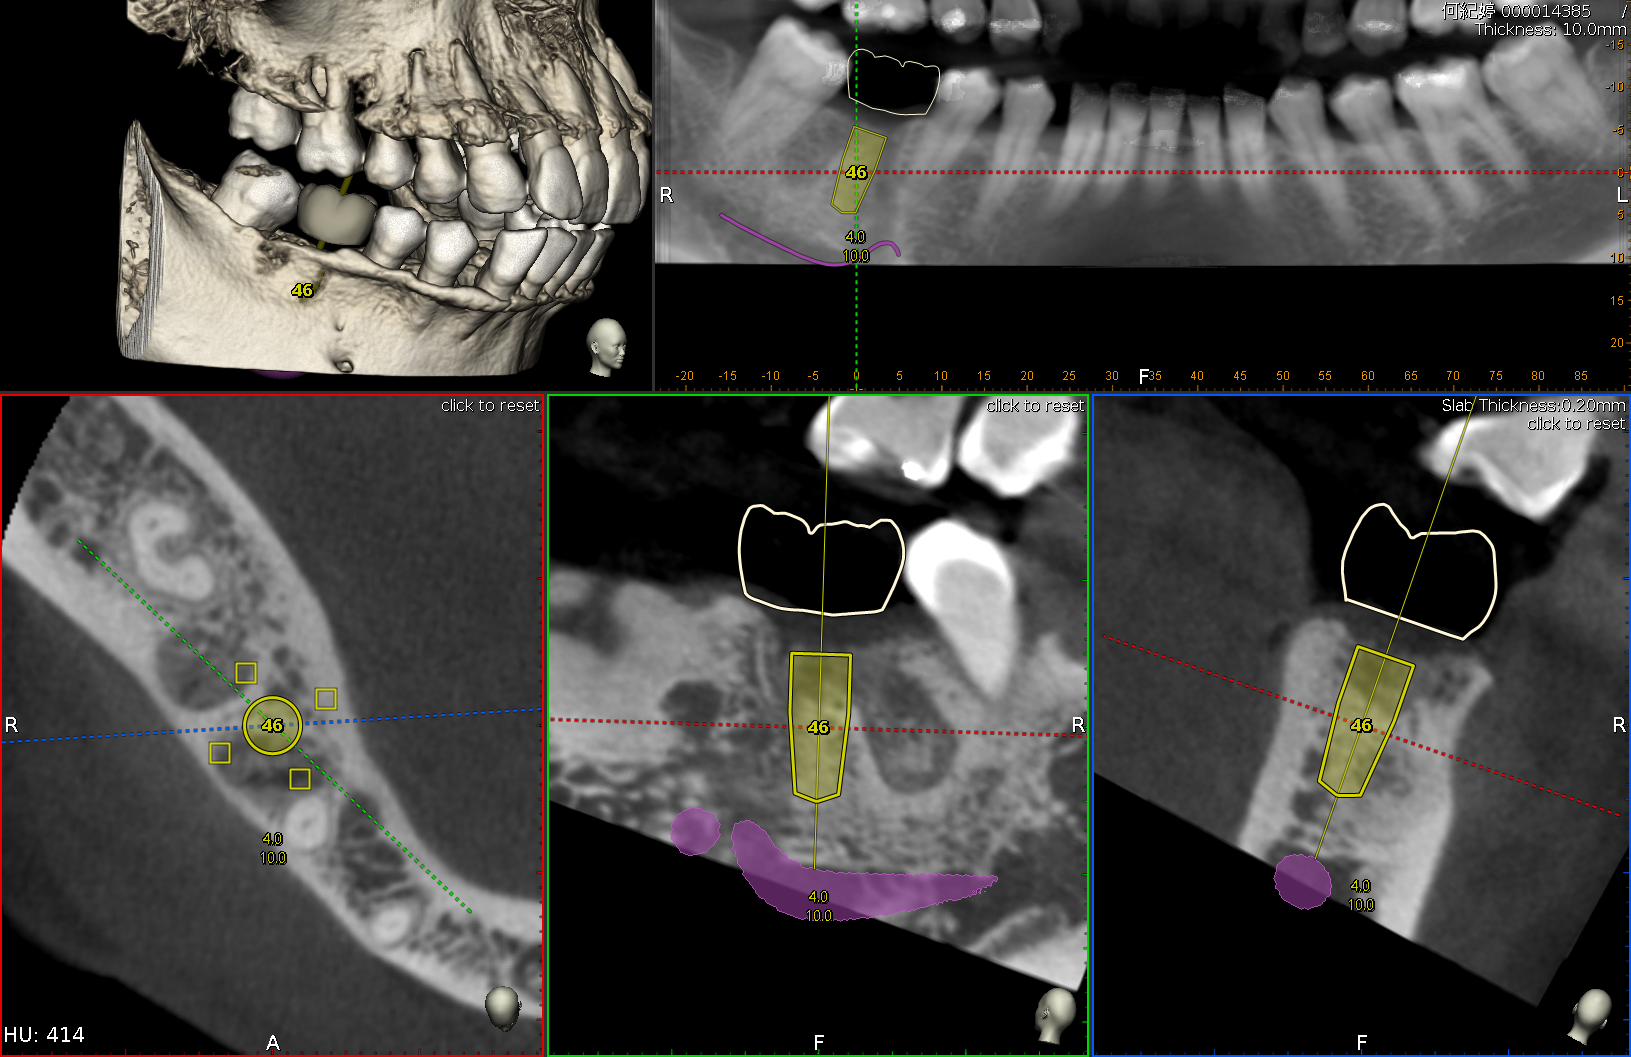

術前模擬

電腦模擬植牙位置,精準安全。

透過3D電腦斷層與口腔掃描,全面檢查牙齒與骨頭狀況,為您量身打造植牙計畫。

利用電腦模擬植牙位置,精準預測手術效果,降低風險,提升成功率。由專科醫師親自操刀,過程舒適、安全,為未來假牙打下穩固基礎。